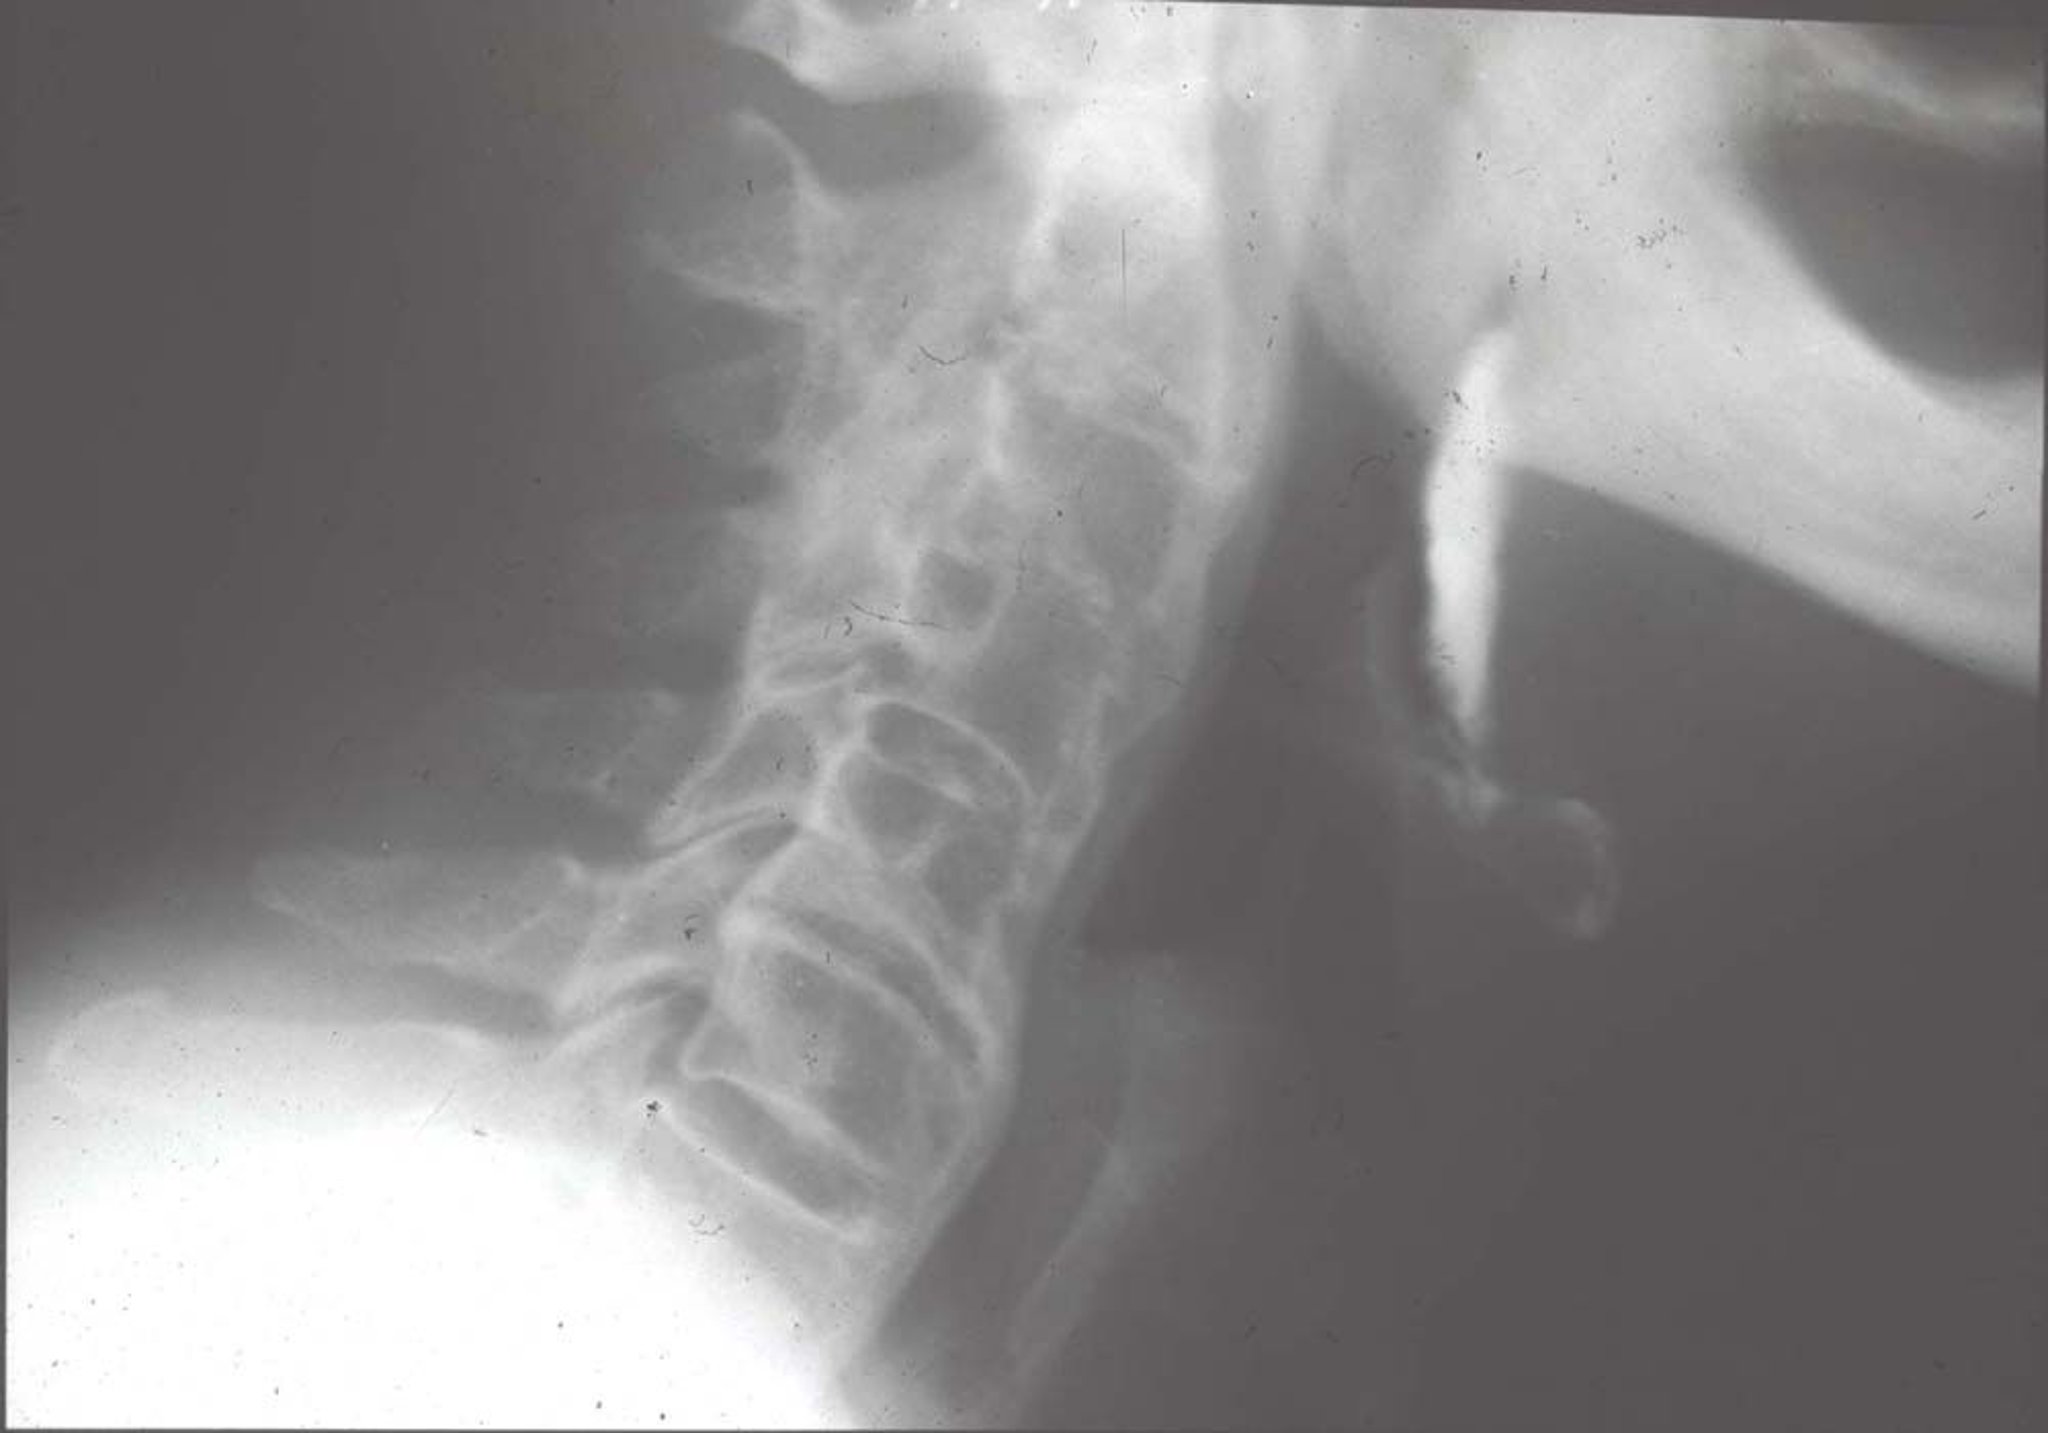

Hiperostosis esquelética idiopática difusa (Radiografía)

Las alteraciones radiológicas características comprenden osificaciones extensas por delante de los cuerpos vertebrales (se asemejan a la "cera de una vela vertida en la parte frontal y lateral de las vértebras"), y abarcan varias vértebras.

Imagen proporcionada por Roy Altman, MD.